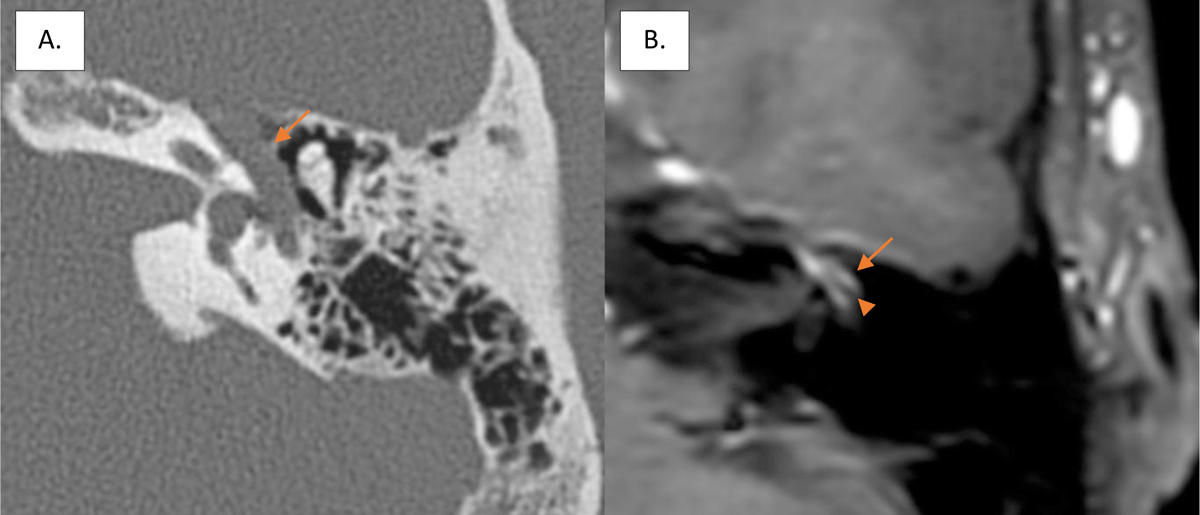

Figure 1

Enlargement of the tympanic segment of the fallopian canal (arrow) on axial CT scan of the left temporal bone (A) and intense contrast-enhancement (arrow) surrounding the facial nerve (arrowhead) on axial gadolinium-enhanced T1-weighted imaging (B).